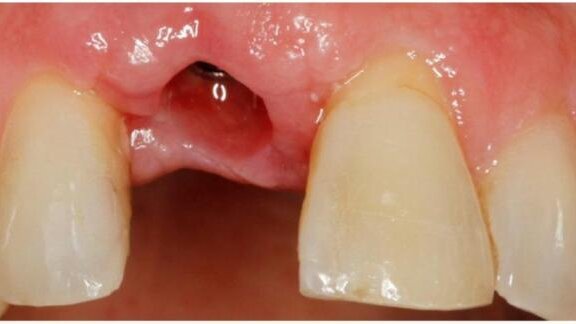

57-letni mężczyzna zgłosił się z powodu utraty przyśrodkowego zęba siecznego szczęki po prawej stronie (ząb 11) na skutek urazu. Pacjent oczekiwał estetycznego, stałego uzupełnienia brakującego zęba, które nie spowodowałoby uszkodzenia zębów sąsiadujących.

Badanie radiologiczne pacjenta wykazało dostateczną ilość kości, umożliwiającą leczenie implantologiczne. Jednak w badaniu klinicznym stwierdzono resorpcję w wymiarze przedsionkowo-podniebiennym, wymagającą augmentacji tkanek twardych. Zatwierdzony przez pacjenta plan leczenia obejmował wszczepienie implantu OSSEOTITE® Tapered PREVAIL® z jednoczesnym zastosowaniem materiału kościozastępczego Endobon® Xenograft Granules i resorbowalnej kolagenowej błony zaporowej OsseoGuard®, a następnie osadzeniem adhezyjnym częściowego stałego uzupełnienia protetycznego, zacementowanego na sąsiednich zębach. Po zakończeniu dojrzewania tkanek twardych i miękkich oraz uzyskaniu osteointegracji, zaplanowano drugi etap postępowania chirurgicznego w celu odsłonięcia implantu, następnie pobranie wycisku cyfrowego łącznika gojącego BellaTek® Encode® w celu wykonania indywidualnego łącznika i korony w systemie CAD/CAM.